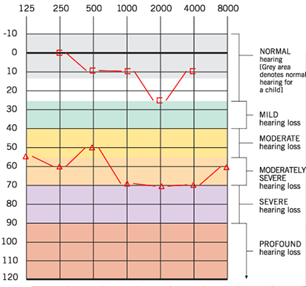

Se realiza tomografía computarizada simple de oídos donde se observa en oído derecho conducto auditivo externo ocupado en su tercio medio por lesión isodensa a hueso, de 8.54 x 8.65 mm, redonda, pediculada de origen en pared anterior, de bordes regulares, sin remodelación ósea, con presencia de material isodenso a tejidos blandos periférico a la lesión, sugestivo de cerumen; oído contralateral sin alteraciones. (Figura 2). Se realizó una audiometría tonal prequirúrgica (Figura 3, 4).

|

| (Figura 3). Audiometría tonal en oído derecho PTA 63.3 GAP 45: Hipoacusia conductiva moderada. | (Figura 4). Audiometría tonal en oído izquierdo PTA 17.85: Normoacusia. |

La paciente fue sometida a una resección quirúrgica por abordaje retroauricular, la lesión se encontraba limitada a la pared anterior del CAE coincidiendo con los hallazgos radiológicos preoperatorios. Se realizó una incisión retroauricular 1 cm por detrás del pliegue retroauricular, con hoja de bisturí #15 se diseca por planos hasta llegar a músculo auricular posterior, el cual se corta y se identifica mediante palpación pared superior e inferior del conducto auditivo externo, se realiza colgajo de Palva y se identifica espina de Henle, área cribosa y sutura timpanomastoidea, se accede a través de dicho colgajo a la piel de la pared posterior del CAE en la cual se realiza incisión cefalocaudal de 1 cm para lograr una exposición completa del CAE y se sostiene el colgajo utilizando un separador dentado. Se visualiza lesión y se elevan colgajos epiteliales superior e inferior al borde más lateral de la lesión, exponiendo de esta manera la cortical de la lesión. Con drill quirúrgico se fresa desde el centro de la lesión hasta quedar únicamente la cortical, obteniendo un “cascarón de huevo”, posteriormente se observa el pedículo de la lesión y se fractura, retirando por completo la lesión ósea, y se fresa la base de la lesión para evitar recurrencia. Posterior a la resección quirúrgica se realiza aseo del CAE, con antibiótico y esteroide, extrayendo restos celulares y se comprueba integridad de la membrana timpánica, se feruliza con Silastic y gelfoam impregnado con corticoide y antibiótico. La paciente presentó una adecuada evolución audiológica corroborada por audiometría tonal, la cual demostró normoacusia en el oído intervenido. Durante las citas postquirúrgicas se evidenció una adecuada cicatrización de tejidos retroauriculares así como los colgajos epiteliales del conducto. La evolución quirúrgica fue favorable, al mes se encontraba asintomática y la audiometría de control reporta normoacusia bilateral. (Figura 5).

| (Figura 5). Audiometría con normoacusia bilateral. |